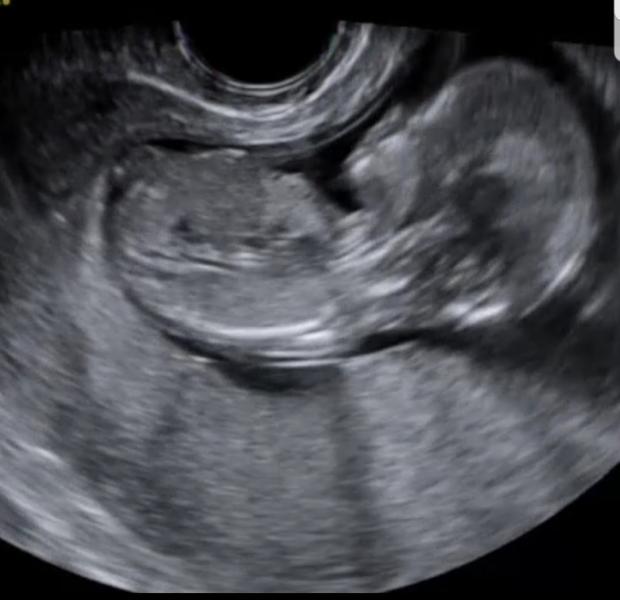

Ровно год назад был такой же прохладный солнечный день. Я поехала на дополнительный скрининг в первом триместре, говорили что плацента низко. Надо было контролировать. И тут мне говорят, что с плацентой всё в норме. И наша любимая с @anastasia_shambratova узистка, которая когда определяет пол ребёнка даже по сердцебиению, не ошибается. Всегда в точку. 😁🤭

Она: Всё-таки спряталась. Это девочка😂💕👸

Боже, после её слов я была вся в слезах от счастья.😭😍

И всю дорогу домой не могла успокоиться. Я всегда знала и чувствовала, что там она 💕 моя синеглазая долгожданная девочка. ❤